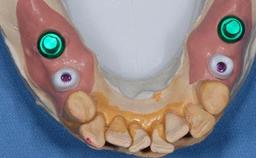

Prosthesis Type FDP

Retention Cemented, with meso-structure Cemented, with meso-structure

Provisional Implant-Supported Prosthesis Prosthodontic margin > 3 mm apical to mucosal margin Prosthodontic margin > 3 mm apical to mucosal margin

Interim Prosthesis during Healing Fixed Fixed